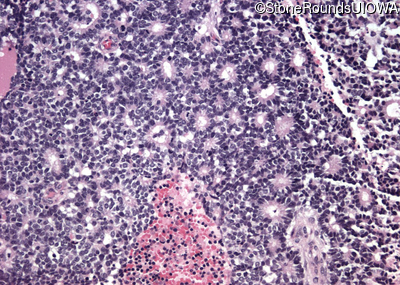

Pathology - Left - -

Exemplar